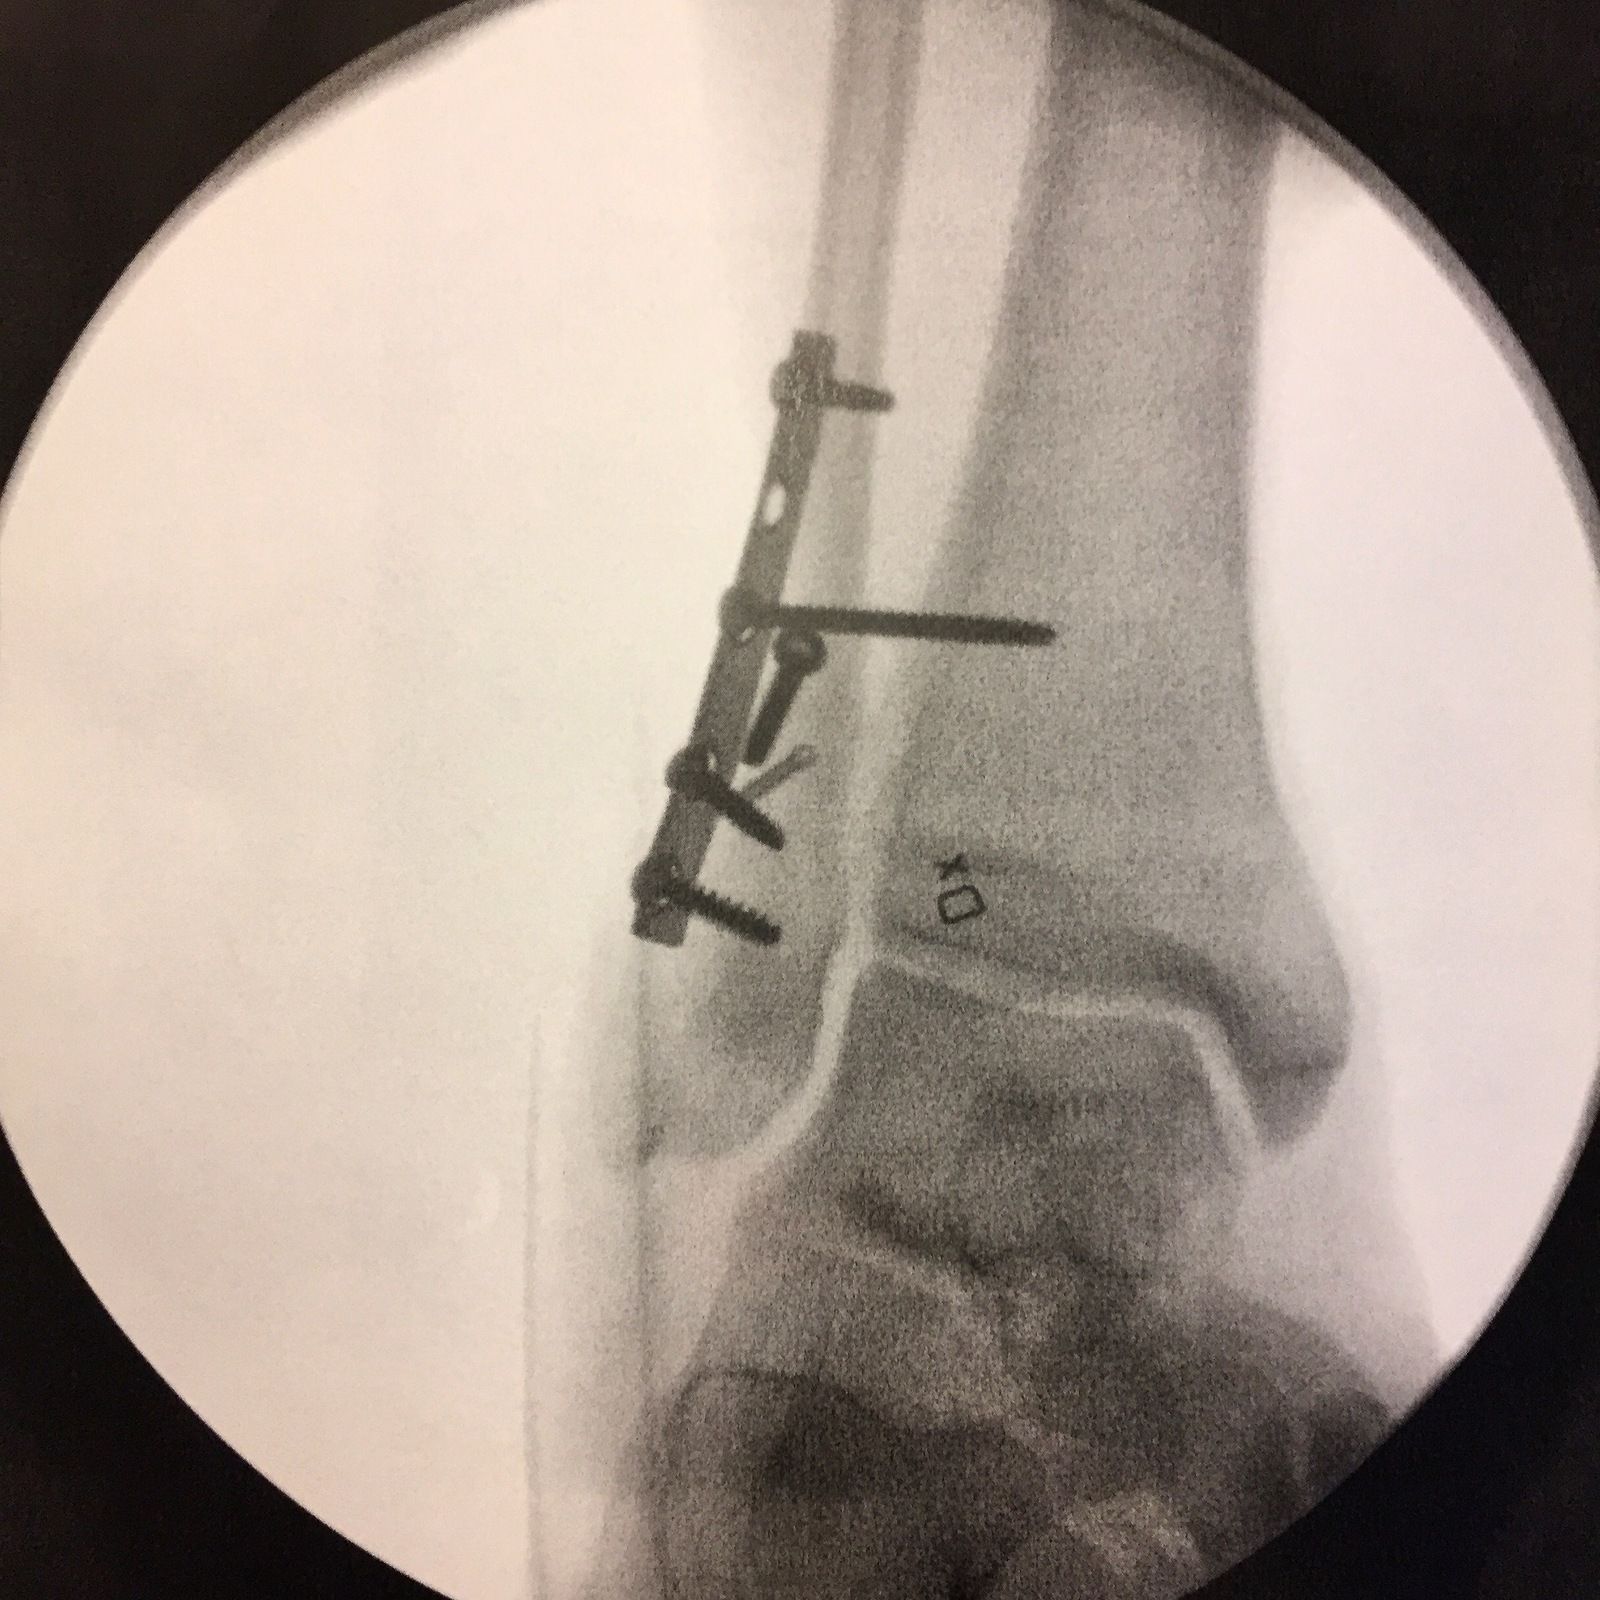

Råkade själv ut för att styre plus hjul vred sig 90 grader när jag passerade en liten oansenlig grop för ett par år sedan, och jag var inte med på noterna. Ena armbågen landade givetvis på en sten.

Läk väl.